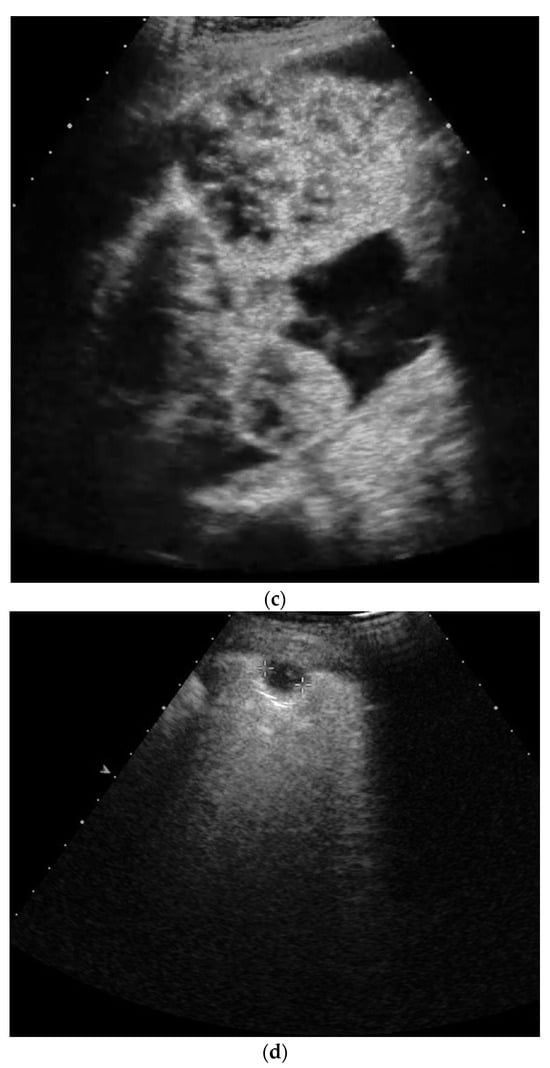

2. Primary Pulmonary Sarcomas